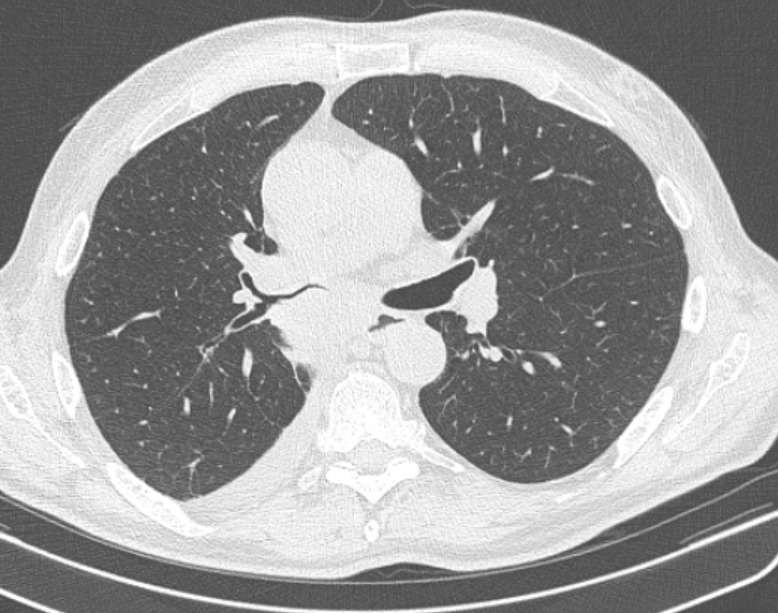

Фото 1 — Центральный рак правого нижнедолевого бронха (1) с обтурацией и метастазами (2) в бифуркационные лимфатические узлы

Периферический рак постепенно сформировывается в боковых отделах легких, медленно прорастая и ничем себя не обнаруживая. Данная опухоль легкого симптомы долгое время может не давать, они появляются при значительном местном распространении, вовлечении соседних органов и структур, прорастания бронхов. Диагностика рака легких этого типа локализации чаще всего возможна при профилактическом обследовании (рентгенографии или компьютерной томографии).

Фото 2 — Периферический рак (1) верхней доли правого легкого